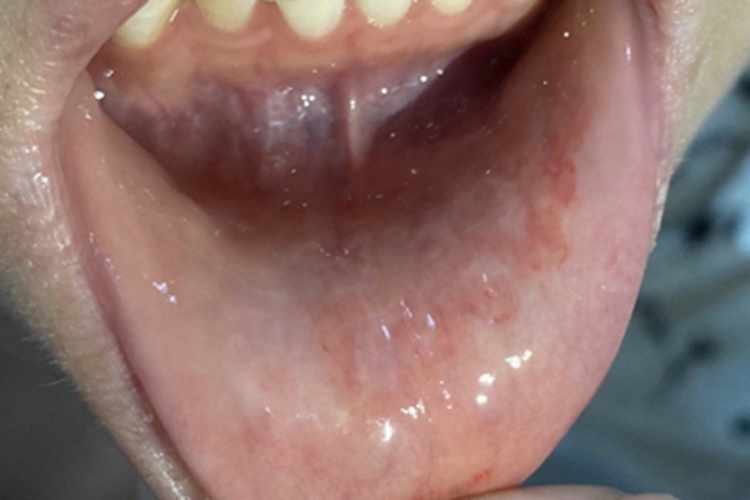

接触性唇炎患者可在唇内侧黏膜出现红色创面,其创面为不规则的形状,边缘清晰,边缘处有红色血丝样,周围黏膜没有明显改变,患者自觉明显疼痛。